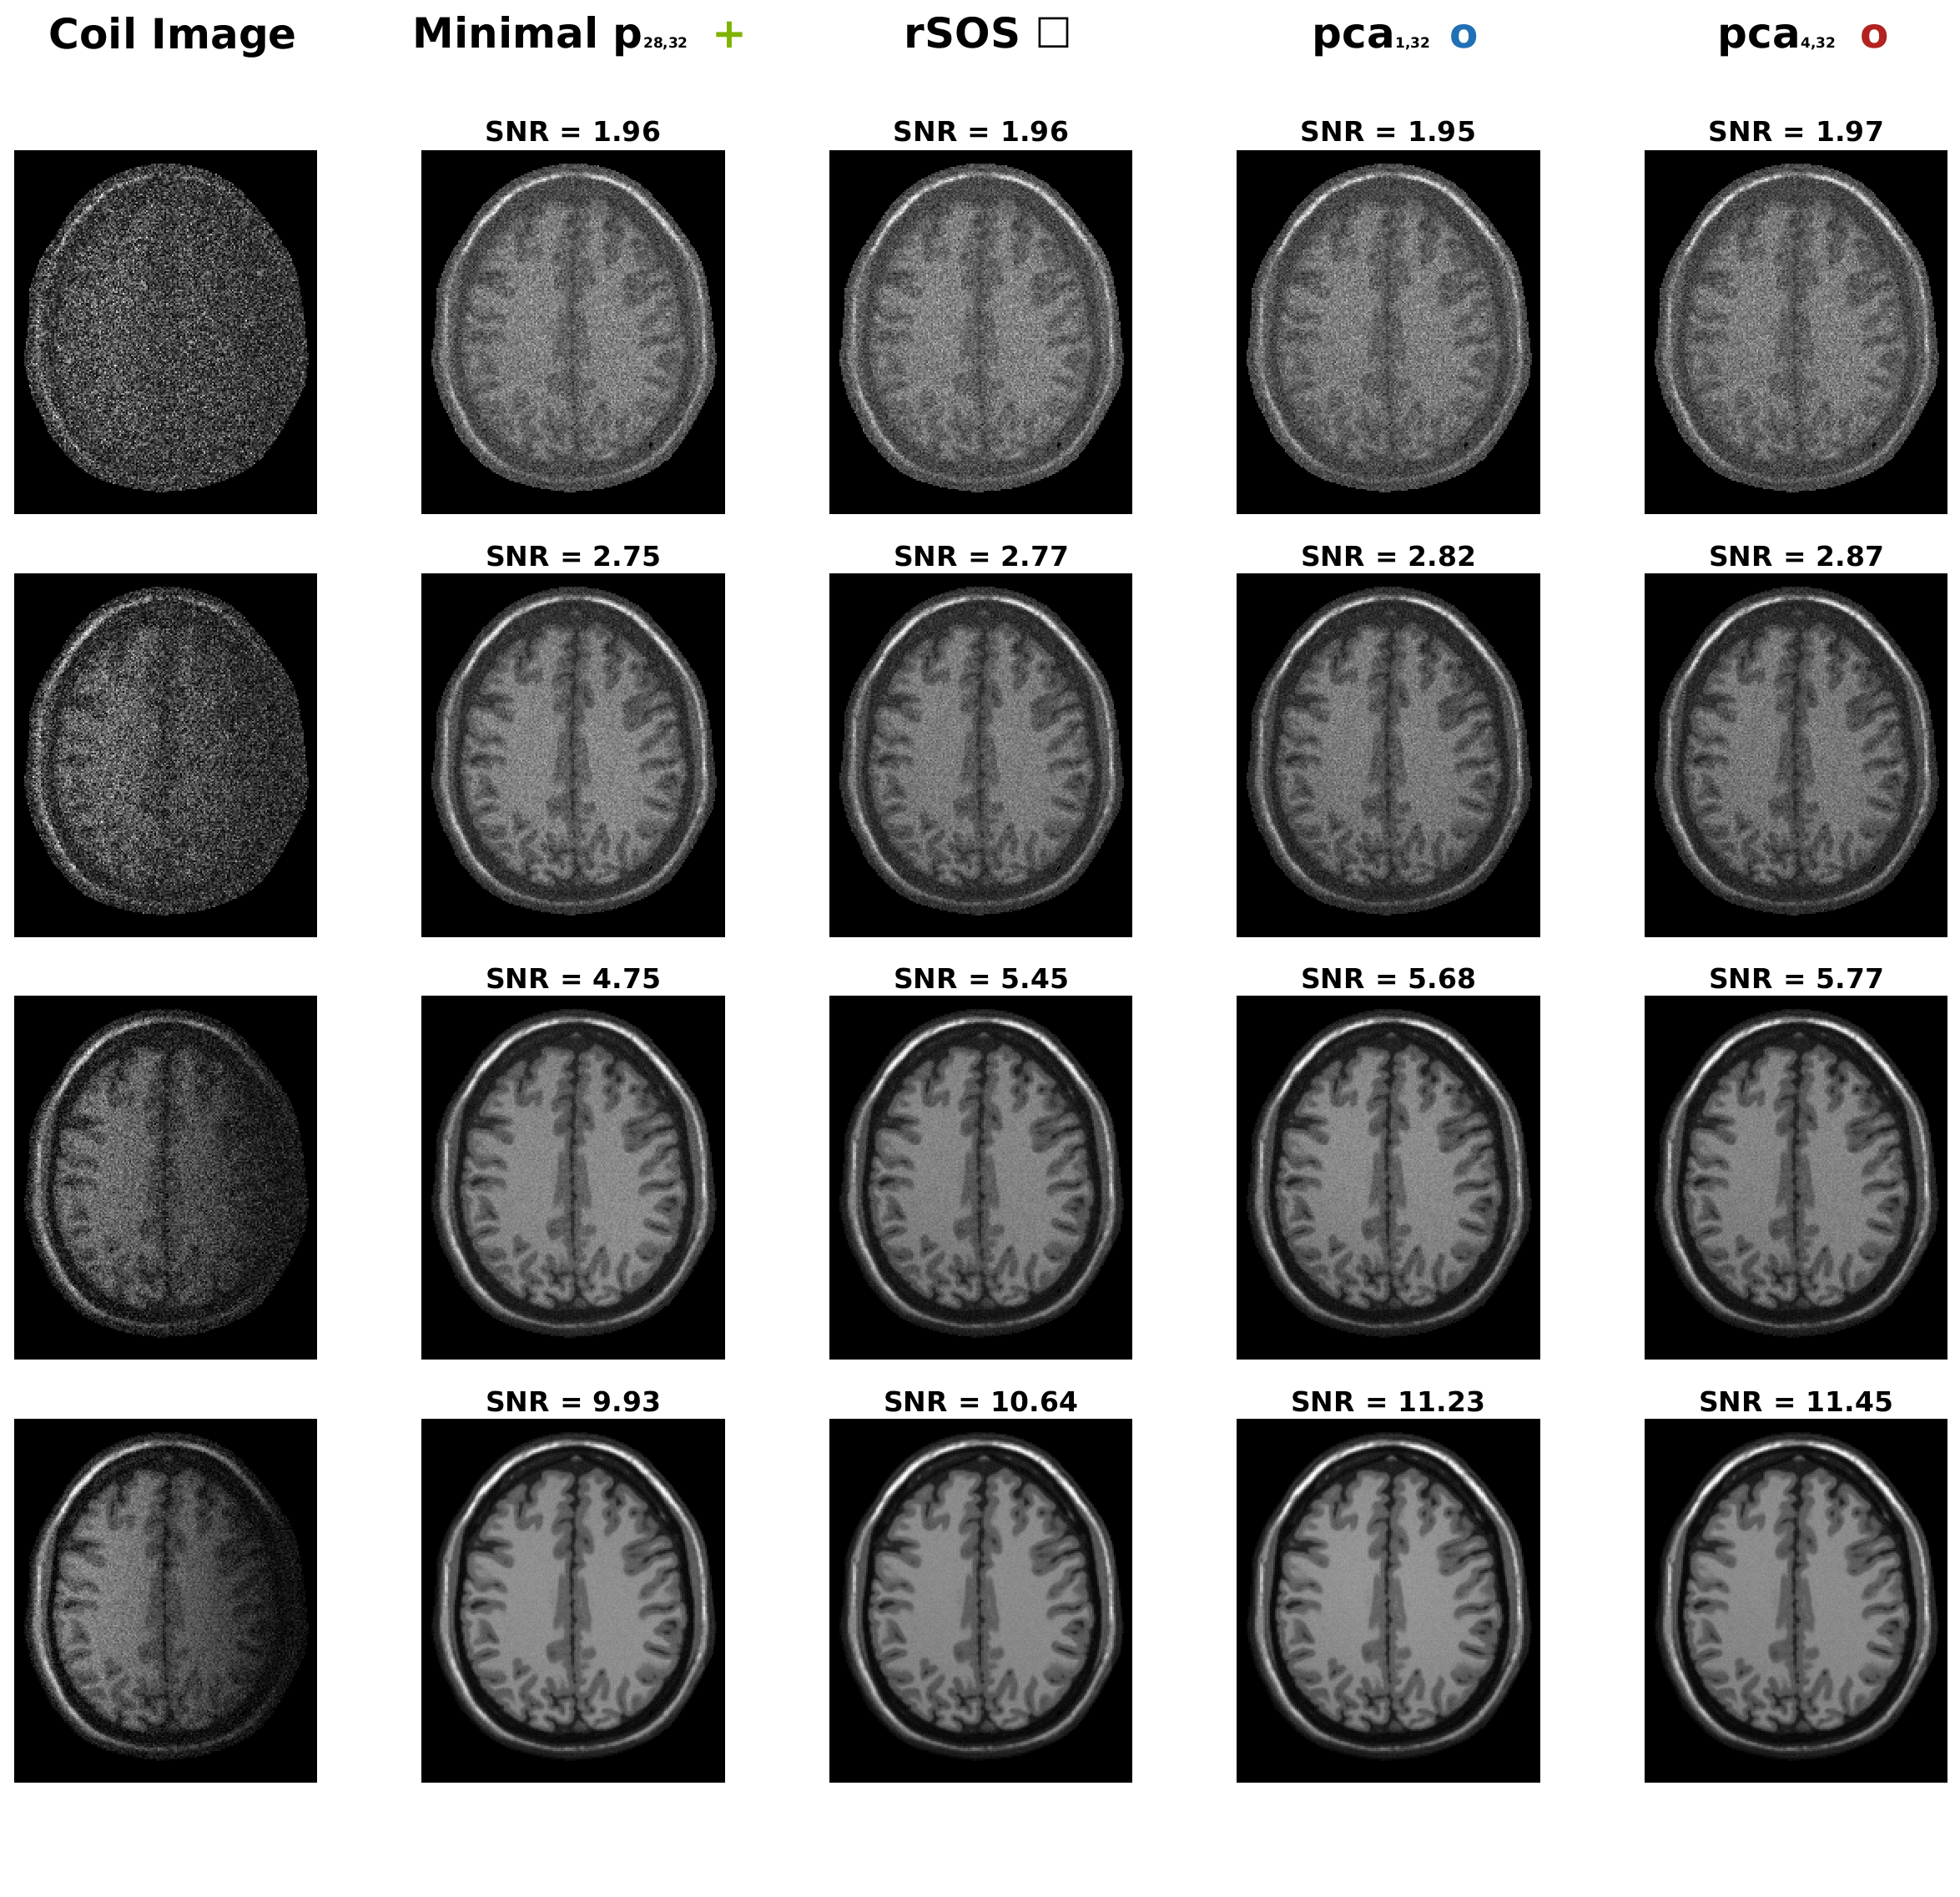

Figure 1 contains the scatter plots for 444 different noise levels in the simulated data set and Figure 2 shows corresponding image cross-sections. Figure 3 shows the scatter plot and image cross-sections of the in-vivo data set.

Refer to caption

Figure 2: Cross-sectional image corresponding to the scatter plots in Figure 1 for the simulated data set with different noise levels. The left column shows the first channel of the simulated noisy 323232-dim coil array before the coil combination step. The second column shows the final image obtained by rSOS including compression with the random projection p𝒢28,32𝑝subscript𝒢2832p\in\operatorname{\mathcal{G}}_{28,32} that yields the minimal L2subscript𝐿2L_{2} reconstruction error (4). The third column shows the image provided by rSOS without compression. The second last columns show the final images when using PCA in 𝒢1,32subscript𝒢132\operatorname{\mathcal{G}}_{1,32} and 𝒢4,32subscript𝒢432\operatorname{\mathcal{G}}_{4,32} for compression, yielding the highest mean SNR. We can directly see that the lowest L2subscript𝐿2L_{2} error does not directly correspond to the highest SNR. Moreover, the visual evaluation suggests that the SNR describes the image quality more accurately.